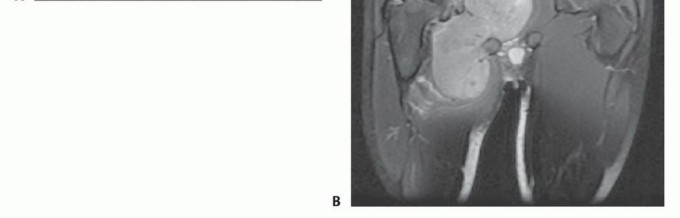

- التشخيص: يتطلب فحصًا شاملاً، تصويرًا متقدمًا (MRI، CT)، وخزعة نسيجية لتأكيد التشخيص وتحديد نوع ودرجة الورم.

- العلاج: يتضمن عادةً الجراحة (الاستئصال الواسع مع الحفاظ على الطرف)، وغالبًا ما يتبعها علاج إشعاعي أو كيميائي لتقليل خطر التكرار أو انتشار الورم.